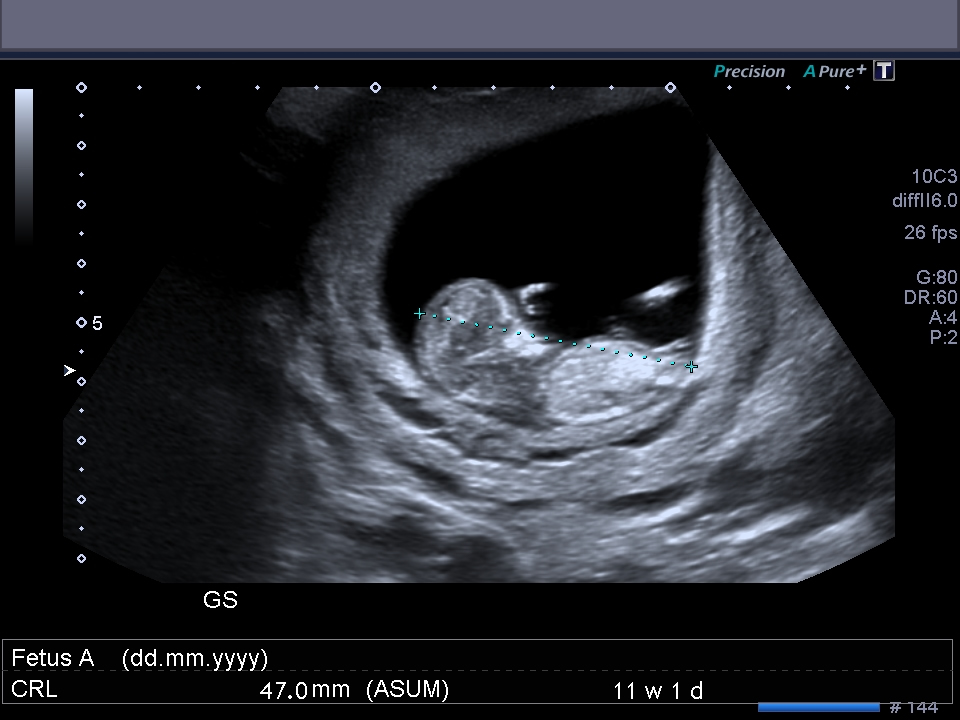

I know these are super early and are not accurate to use but I thought I would post them just for fun and see what everyone thinks :) Thanks xo

Congrats! What a cute babe :)

As a just for fun guess, given how early it is, I’d lean girly! ;)

Omg, you're already this far?! Time flies so fast haha!! Beautiful baby! Also super early but I say girly because of that forking ;)

Good luck, very early but girlie (my little one had a similar looking fork at 11+6 and have found out it's a girl so fingers crossed for you).